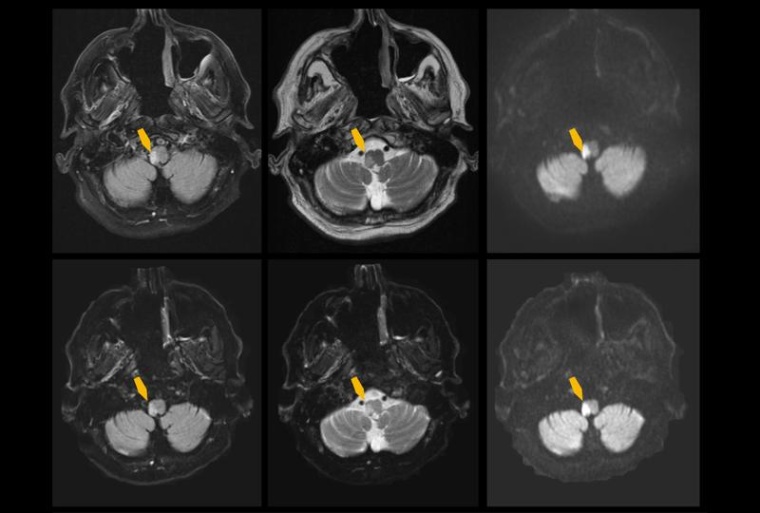

Dabei setzten sie einen Deep Learning-Algorithmus für die Bildrekonstruktion ein. Im Vergleich zur konventionellen MRT konnten die MRT-Bilder viermal schneller rekonstruiert werden. Zudem erzielte die KI-gestützte MRT eine höhere Bildqualität, so dass auch leichte Schlaganfälle zuverlässiger erkannt werden konnten. Die neue Methode hat großes Potential, die Notfalldiagnostik zu beschleunigen, um Patienten mit Schlaganfall-Verdacht schneller behandeln zu können. Das berichten die Wissenschaftler anlässlich des Tags gegen den Schlaganfall am 10. Mai. Die Forschungsergebnisse wurden im Journal „Radiology“ veröffentlicht.

In seiner prospektiven Studie hat das Forschungsteam 211 Patienten mit Verdacht auf einen akuten ischämischen Schlaganfall mit der konventionellen MRT sowie der neuen KI-beschleunigten MRT untersucht. Insgesamt benötigte die konventionelle MRT eine Untersuchungszeit von rund 14 Minuten. Diese konnte durch den Einsatz von Deep Learning um das Vierfache, auf etwa drei Minuten reduziert werden.

Die Deep Learning-gestützte MRT lieferte verglichen mit der konventionellen Methode insgesamt eine bessere Bildqualität. Beide Methoden zeigten eine gute bis ausgezeichnete Zuverlässigkeit, um einen akuten ischämischen Infarkt zu diagnostizieren. Wobei eine exzellente diagnostische Sicherheit in 96 % der Fälle durch die neuartige Methode erzielt werden konnte (konventionellen Methode 92 %).